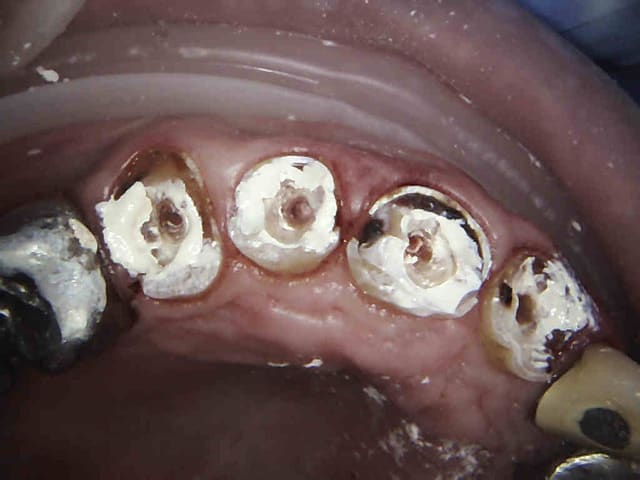

Avantage tu peux faire les provisoires et l'empreinte dans la séance et surtout tu peux raser les couronnes ce qui est un réel plus pour les endos surtout avec des pulpes rétractées comme ici ca évite de faire des conneries avec un abord palatin ou on ne voit rien du tout.

Il n'y avait pas grand chose à raser de toutes façons ! Et avec notre nomenclature de merde un inlay core comprime le reste à charge. Voilà ce qui se passe quand un assureur se mêle de tarifs. En France plus on défonce les dents et plus c'est remboursé.